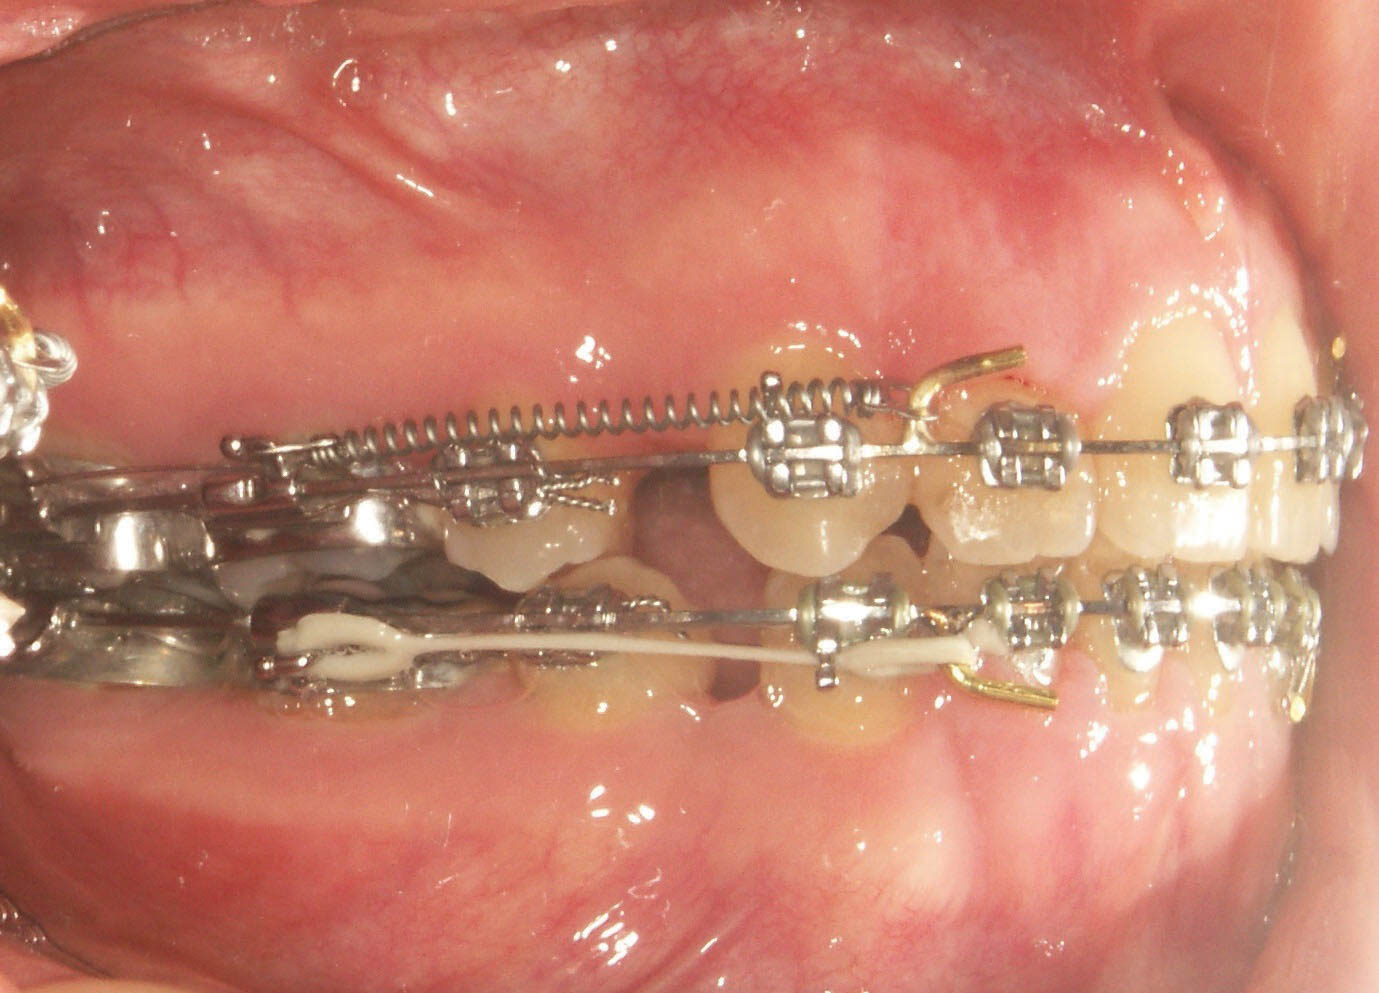

برای بستن فضاهای خلفی عالی است. باید سیم شما استیل هوکدار باشد. یک نیرویی بین هوک خلفی و قدامی مانند یک قطعه فنر بسته بگذارید. این نیرو باعث کم شدن فاصله دو هوک میشود یعنی سگمنت خلف و قدام حرکت میکنند تا بهم نزدیک شوند. سگمنت قدام به صورت گروهی حرکت میکند و عقب میرود. دندانها دیگر روی سیم حرکت نمیکنند تا باعث بروز اصطکاک بین براکت و سیم بشود بلکه دندان و براکت بهمراه خود سیم همه با هم حرکت میکنند. سیم درون شیار براکت 5 و6 و 7 میلغزد و عقب میرود به همین دلیل به این روش لغزشی میگویند (شکل 24-4). طبیعی است که هنوز مقداری اصطکاک بین سیم و براکت 5 و 6 و 7 وجود دارد به همین خاطر با قرار دادن سیم استیل در دو الی سه ماه اول شروع به بستن فضا نمیکنیم تا سیم درون براکت 5 و 6 و 7 جابیفتد و Tip و Torque این سه دندان بهتر بشود و اصطکاک به حداقل برسد و در جلسات بعدی شروع به بستن فضا میکنیم.

در دو سه ماه اول یک Passive Tieback بزنید. بعد که آرچوایر راحت کف براکت قرار گرفت و دندانها به حداکثر زوایای تیپ و تورک رسیدند، Passive Tieback را قطع کنید و خارج نمایید. دندان پرمولر را هم وایر لیگاچور نمایید (شکل 25-4) تا اصطکاک سیم با براکت آن به حداقل برسد و بعد بستن فضا شروع میشود.

شکل 24-4: در بستن فضا به روش لغزشی از سیم هوک دار استفاده میشود و کل سیم از درون شیار براکت 5 و6 و7 به سمت عقب حرکت میکند.

شکل 25-4: وایر لیگاچور براکت 5 قبل از شروع بستن فضا